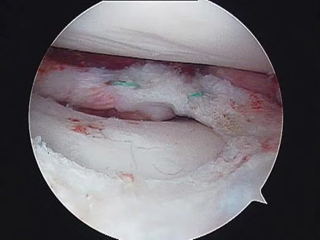

先天性盘状半月板是儿童好发病,常常导致膝关节伸直受限和疼痛,出现症状需要及早手术处理,微创关节镜下修整成型是保留半月板的最佳方式。

先天性盘状半月板